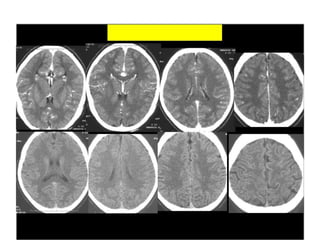

CT SCAN OF BRAIN

Ct scan lecture